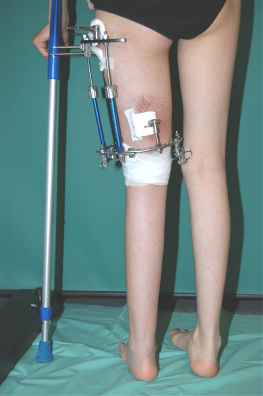

Therapie: Verlängerung des linken Oberschenkelknochens mittels Distraktionsverfahren nach Ilisarow um 18 cm Anpassende Verkürzung des rechten Oberschenkelknochens um 3cm

Behandlungszeitraum: 01.02.2005-11.09.2006